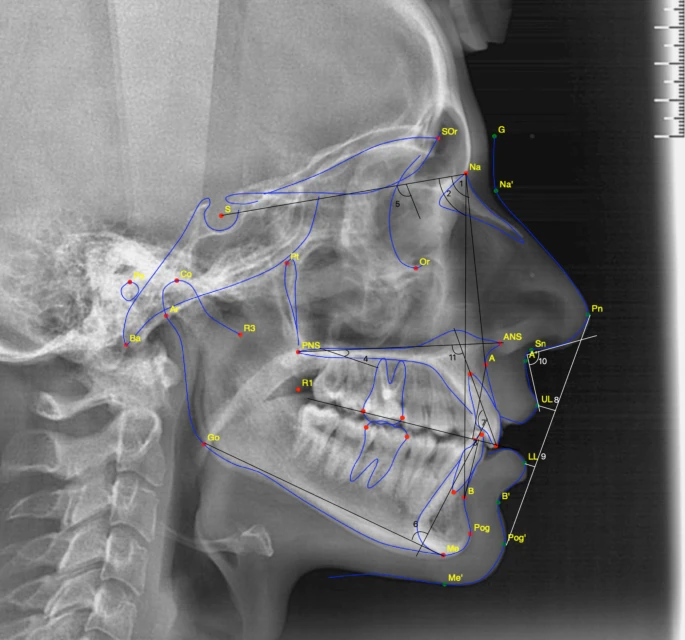

Digital Imaging

Quick, comfortable CBCT and photos to see the complete picture of your child's smile.

Our orthodontist examines your child's teeth, jaw, and bite in a comfortable, pressure-free setting.